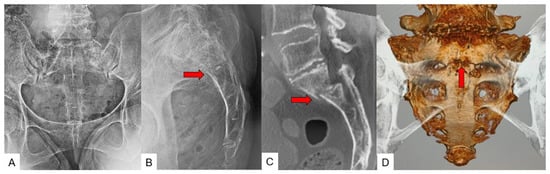

3.4. Typical SIF Case